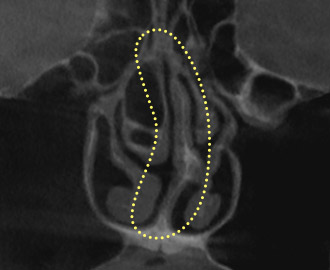

Deviated Nasal

Septum

A deviated nasal septum

occurs when

the cartilage

located at the center of

the nose bends, causing

functional

issues such

as nasal congestion,

rhinitis, and sinusitis.

Treatment Points

Remove the curved septal

cartilage and bone, then

straighten the septal

cartilage

to correct the

shape properly.

3D-CT Examination

Before surgery, a 3D-CT scan is conducted to accurately capture internal

nasal structures, including the skeletal structure, nasal bone width, septal

condition, asymmetry, and inferior turbinate size, which are difficult to

observe with the naked eye